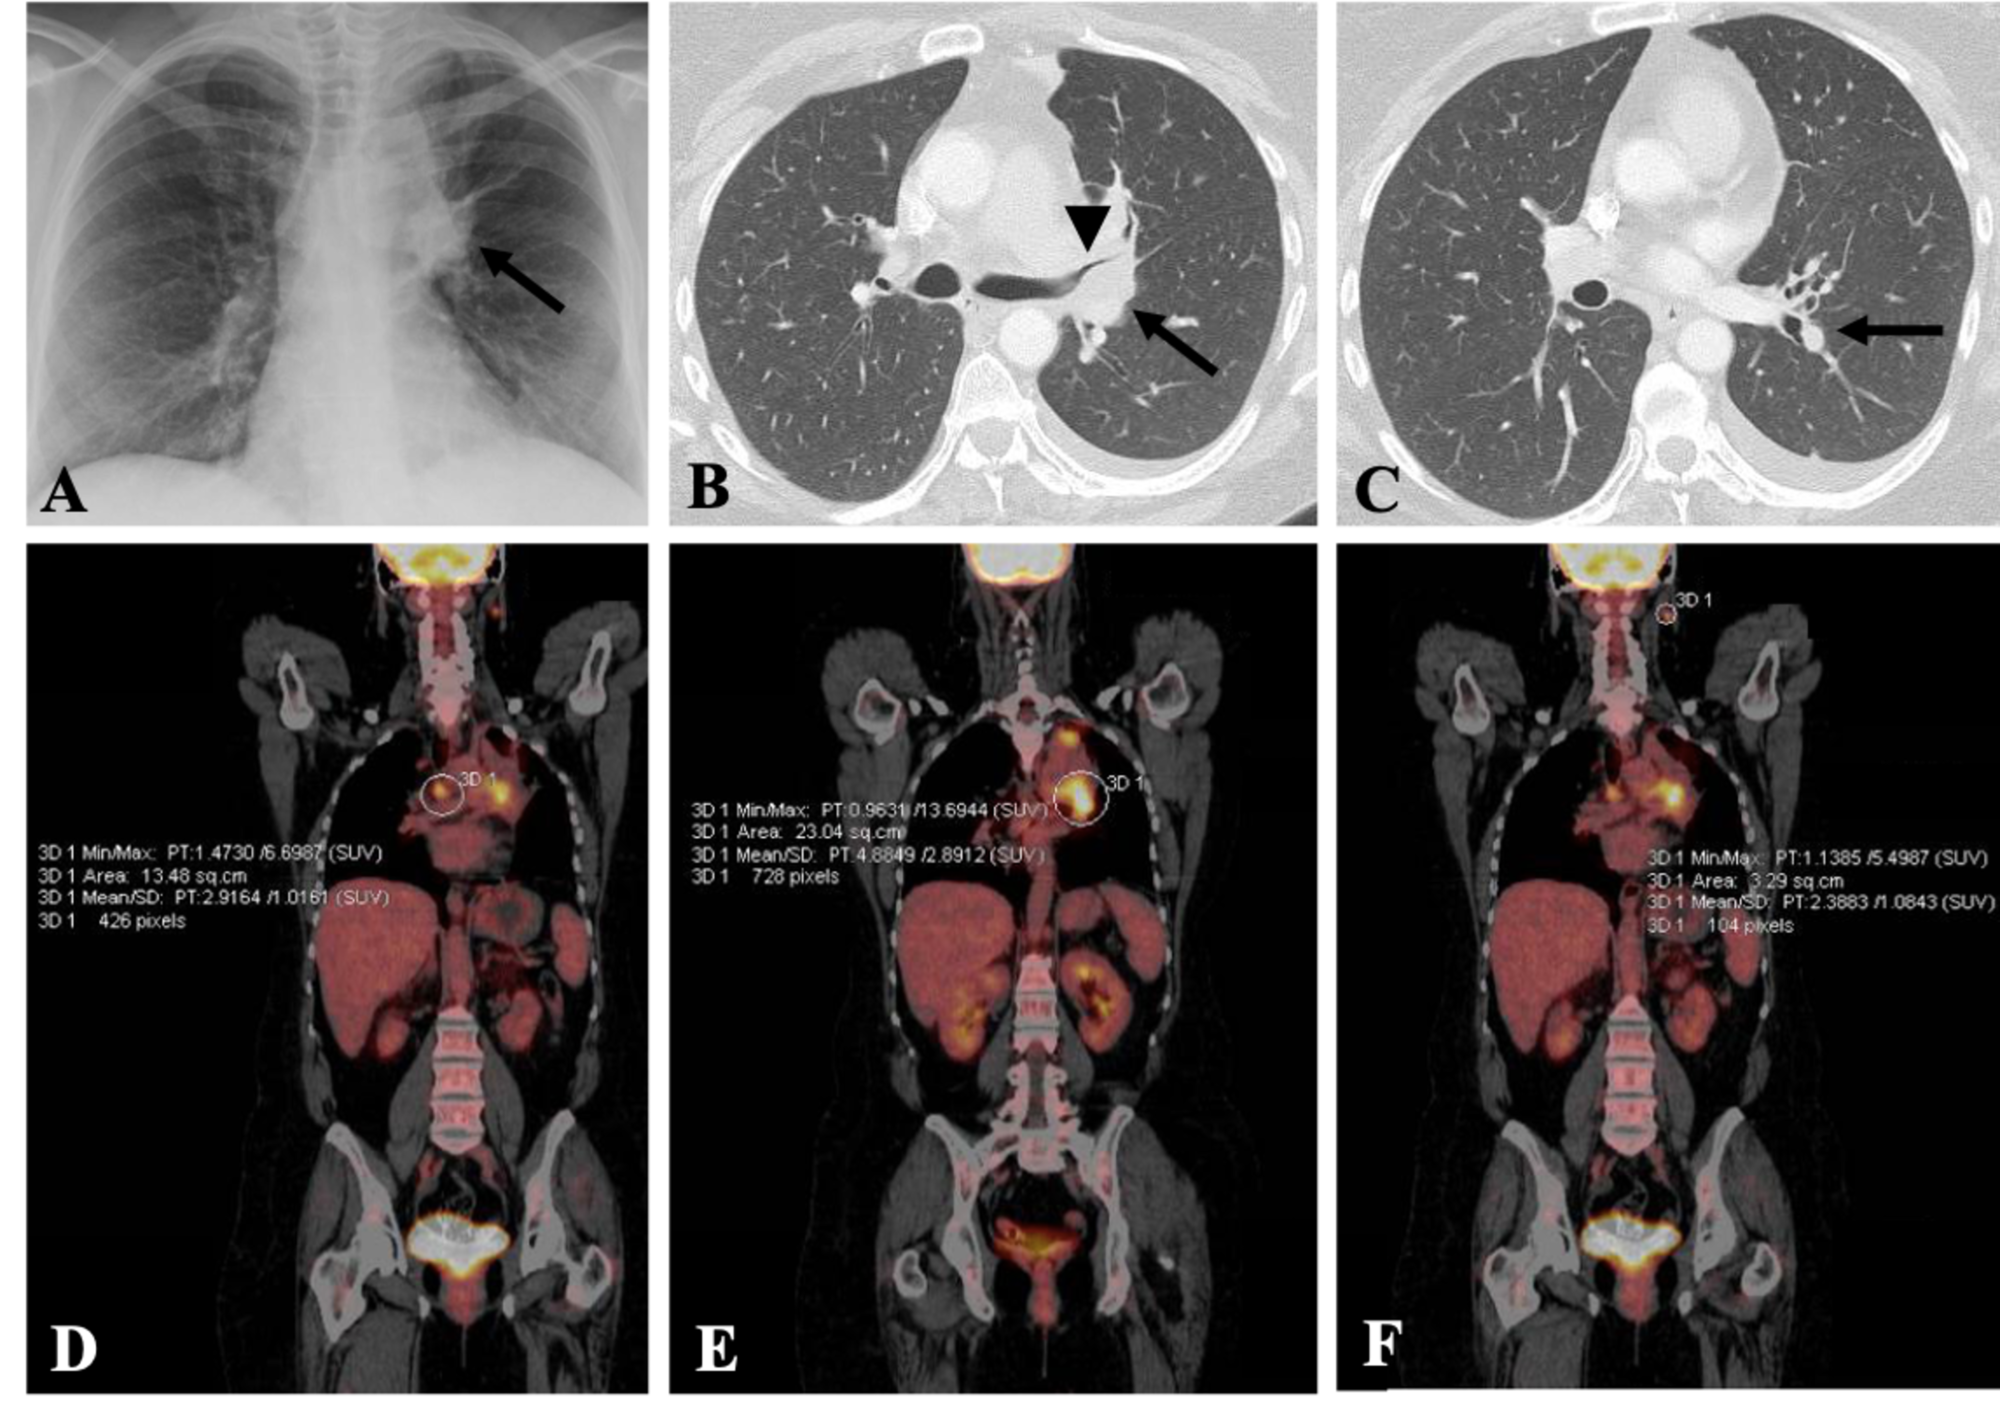

From www.cureus.com

Cureus Adenocarcinoma of the Lung Presenting with Intrapulmonary Chest X Ray Metastatic Cancer — chest radiography (cxr) is the initial imaging modality used in the detection of suspected pulmonary metastasis in patients. — when cancer cells travel to other organs in the body, it’s called metastasis. Another term for metastatic cancer to the lungs is secondary cancer in the lungs, as the primary cancer is the place in the body where. Chest X Ray Metastatic Cancer.